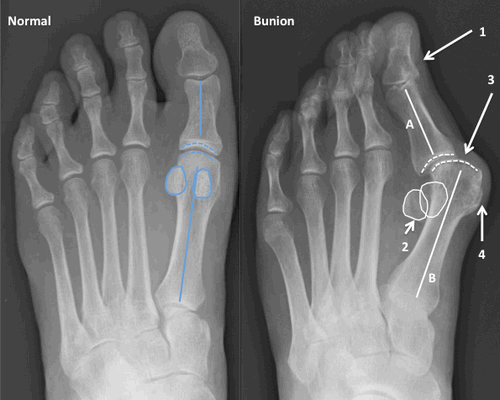

Поперечный свод стопы образован головками I-V плюсневых костей. В норме они образуют своеобразную арку. Поперечный свод поддерживается связками, сухожилиями и головкой мышцы, приводящей большой палец стопы. При нарушении мышечно-связочного баланса у человека возникает поперечное плоскостопие. Как правило, оно осложняется вальгусной деформацией I пальца стопы.

По статистике, Hallux Valgus разной степени выявляют у 100% пациентов с поперечным плоскостопием. Во время хирургического вмешательства врачам приходится одновременно устранять обе патологии.